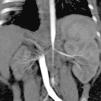

Case 3PresentationFemale infant aged 4 months with a prenatal diagnosis of hypertrophic cardiomyopathy (initially attributed to intrauterine closure of the ductus arteriosus), admitted to the paediatric intensive care unit due to a hypertensive crisis (at-home BP of 180/110 mmHg). Absence of a palpable femoral pulse or audible bowel sounds in the physical examination. A renal scintigraphy and CT angiogram of the abdominal aorta revealed a hypoplastic right kidney with decreased function (differential renal function, 9.7%) and a substantially decreased diameter of the abdominal aorta below the level of the superior mesenteric artery and narrowing of the renal arteries at the origin (Fig. 1).

Clinical course and outcomePharmacotherapy was initiated with amlodipine and propranolol, and the patient was referred to an international reference centre, where she underwent an angioplasty at age 6 months. After the surgery, there were signs of improvement of the hypertrophic cardiomyopathy. The follow-up angiogram found that the calibre of the renal arteries had increased (diameters of 2.5 and 2 mm vs previous diameters of 2 and 1.3 mm). At age 20 months, the patient underwent a second angioplasty. Currently, at age 3 years, the patient exhibits adequate control of BP with a single drug (atenolol).

DiagnosisMid-aortic syndrome. This term refers to the segmental narrowing of the abdominal aorta and its branches, chiefly the renal arteries.6 The associated HTN is usually severe and poses a therapeutic challenge that may require multiple drugs and open or endovascular surgery.